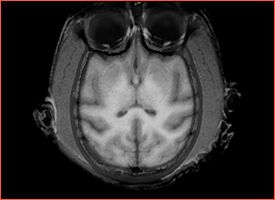

Fat shift artifact significantly obstructs the cortex in the occipital lobe for all subjects